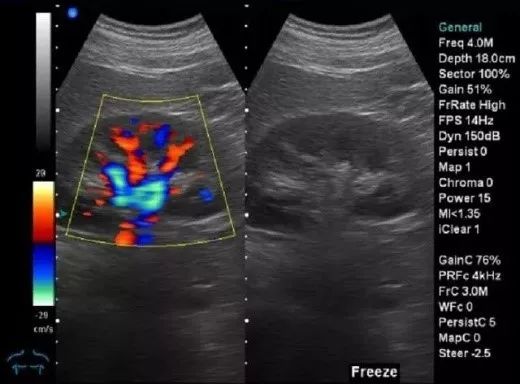

B超

辐射:无

B超的原理是用超声波穿透人体,当声波遇到人体组织时会产生反射波,通过计算反射波呈像。就像挑西瓜一样,边敲边看显示病灶情况,完全没有辐射。